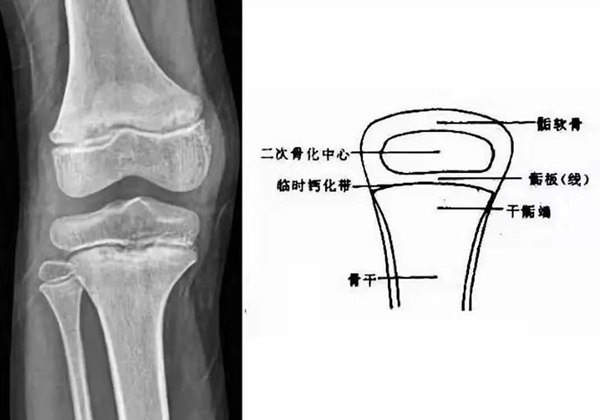

我們都知道,人體的高矮是由骨骼的生長(zhǎng)發(fā)育決定的,特別是下肢長(zhǎng)骨。長(zhǎng)骨呈長(zhǎng)管狀,在長(zhǎng)骨的兩端有一種專管骨骼生長(zhǎng)的骺軟骨,它與干骺端之間有一盤(pán)狀軟骨結(jié)構(gòu)稱為骺板(線),在幼兒的X光片上表現(xiàn)為一條較寬的透光帶。 (見(jiàn)下圖)

未成年時(shí)隨著年齡的增加骺軟骨端不斷骨化,骨骼就不斷增長(zhǎng)。當(dāng)骨骺線完全閉合時(shí)骨骼就停止生長(zhǎng),個(gè)子也就不再增長(zhǎng)了。一般骨骺端完全閉合的年齡是18~20歲左右。